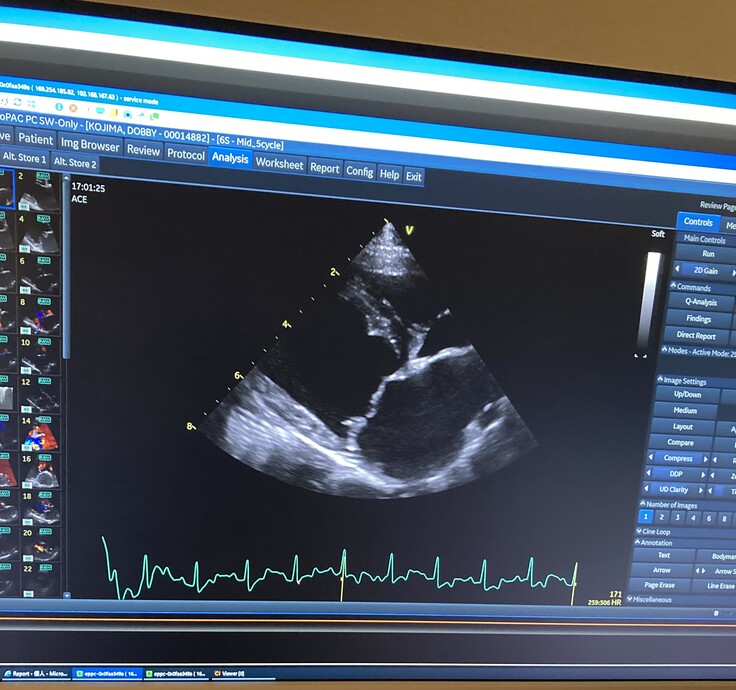

▼心臓のエコー画像

父親や兄と同じ病を患うドビーが、今現在では ステージC に入ってしまっており、酷くショックなことに

今回検査を受けた手術先の病院で、「8ヶ月をめどに見ておいてください。」と余命宣告をされました。

ドビーの場合は、僧帽弁が数カ所”切れてしまっている状態”らしく、

今は心臓が、めいっぱいの状況で頑張ってくれているそうなのです。